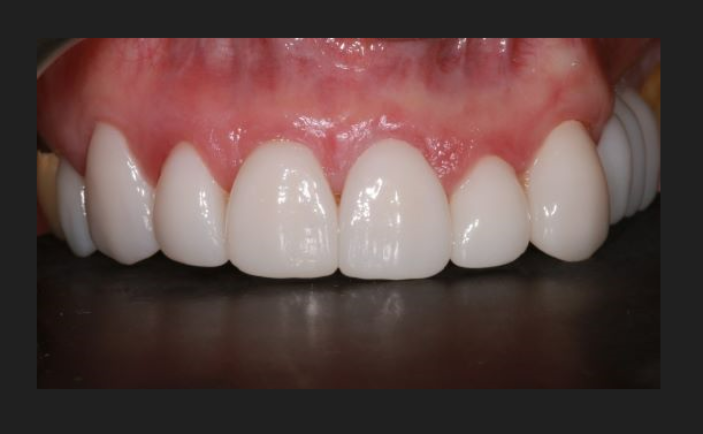

Our implants are made from biocompatible titanium and are fitted directly into the jawbone to replace the root of the tooth. Porcelain replacement teeth will then be handcrafted to match your existing teeth, either from photographs or a visit to our local technician.

It usually takes between three and six months to get your permanent porcelain replacement teeth, however we’ll ensure you’ll never be left with a gap, with temporary tooth solutions available in-between.